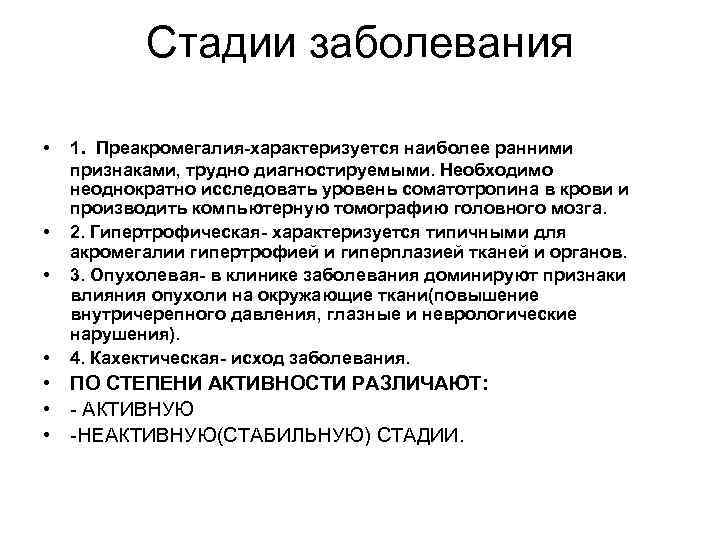

Стадии заболевания • • 1. Преакромегалия-характеризуется наиболее ранними признаками, трудно диагностируемыми. Необходимо неоднократно исследовать уровень соматотропина в крови и производить компьютерную томографию головного мозга. 2. Гипертрофическая- характеризуется типичными для акромегалии гипертрофией и гиперплазией тканей и органов. 3. Опухолевая- в клинике заболевания доминируют признаки влияния опухоли на окружающие ткани(повышение внутричерепного давления, глазные и неврологические нарушения). 4. Кахектическая- исход заболевания. • ПО СТЕПЕНИ АКТИВНОСТИ РАЗЛИЧАЮТ: • АКТИВНУЮ • НЕАКТИВНУЮ(СТАБИЛЬНУЮ) СТАДИИ.

Стадии заболевания • • 1. Преакромегалия-характеризуется наиболее ранними признаками, трудно диагностируемыми. Необходимо неоднократно исследовать уровень соматотропина в крови и производить компьютерную томографию головного мозга. 2. Гипертрофическая- характеризуется типичными для акромегалии гипертрофией и гиперплазией тканей и органов. 3. Опухолевая- в клинике заболевания доминируют признаки влияния опухоли на окружающие ткани(повышение внутричерепного давления, глазные и неврологические нарушения). 4. Кахектическая- исход заболевания. • ПО СТЕПЕНИ АКТИВНОСТИ РАЗЛИЧАЮТ: • АКТИВНУЮ • НЕАКТИВНУЮ(СТАБИЛЬНУЮ) СТАДИИ.